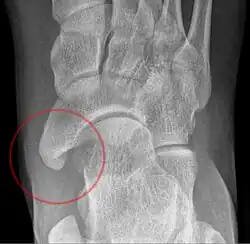

X-ray of the foot showing an accessory navicular bone

An accessory navicular bone is an accessory bone of the foot that occasionally develops abnormally in front of the ankle towards the inside of the foot. This bone may be present in approximately 2-14% of the general population and is usually asymptomatic.[1][2][3] When it is symptomatic, surgery may be necessary.

The Geist classification divides the accessory navicular bones into three types.[3]

• Type 1: An os tibiale externum is a 2–3 mm sesamoid bone in the distal posterior tibialis tendon. Usually asymptomatic.

• Type 2: Triangular or heart-shaped ossicle measuring up to 12 mm, which represents a secondary ossification center connected to the navicular tuberosity by a 1–2 mm layer of fibrocartilage or hyaline cartilage. Portions of the posterior tibialis tendon sometimes insert onto the accessory ossicle, which can cause dysfunction, and therefore, symptoms.

• Type 3: A cornuate navicular bone represents an enlarged navicular tuberosity, which may represent a fused Type 2 accessory bone. Occasionally symptomatic due to bunion formation.